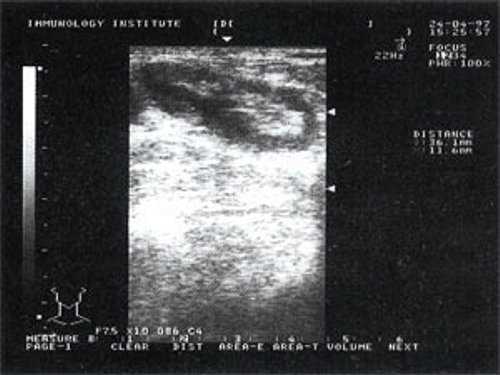

Мы выявили совершенно другую УЗ-картину состояния пальпируемых лимфатических узлов при динамической оценке у больных с синдромом иммунодефицита. Оцениваемые лимфатические узлы имели эхографические признаки доброкачественного процесса, в большинстве наблюдений их размеры превышали 2-2,5 см. При этом во всех случаях дифференцировались составные части лимфатического узла. Определялся узкий кортикальный слой и широкая гиперэхогенная сердцевина при сохранении овальной конфигурации и соотношении поперечного/переднезаднего более 1.

При повторных УЗ осмотрах на фоне массированной противовоспатительной терапии было отмечено увеличение числа лимфатических узлов вовлеченных в процесс активизации. При этом заметной перестройки эхоструктуры и уменьшения размеров в наблюдаемых лимфатических узлах отмечено не было (рис 4).

Рис. 4. Варианты изображения увеличенного лимфатического узла с УЗ-признаками доброкачественной аденопатии у больного с синдромом иммунодефицита.